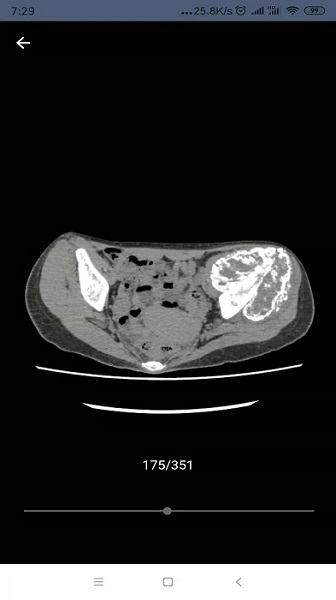

将二维医学影像图片重构成一个三维模型的软件,方便用户更直观观看重构部位。更是更直观的理解医院影的像内容。用户仅需简单的将数据上传至我们的服务器,重建完成后我们将通知您,然后再此软件上进行查看。

重建模型,可以便捷的查看非常形象的可视化三维模型,利于掌握病情;

提供基于ct、mri二维医学影像的三维重建技术服务。

本软件是可以将,医学影像图片,重构成一个三维模型的软件。

各个部位的二维医学影像图片都可以通过简单的方式进行转换;

画质非常的清晰,便于用户根据反馈的三维模型进行详细观察;